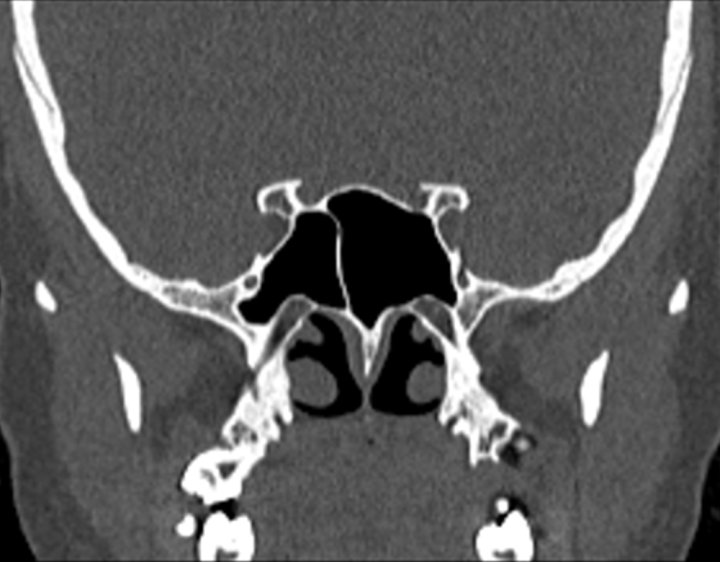

Click any image for labels.